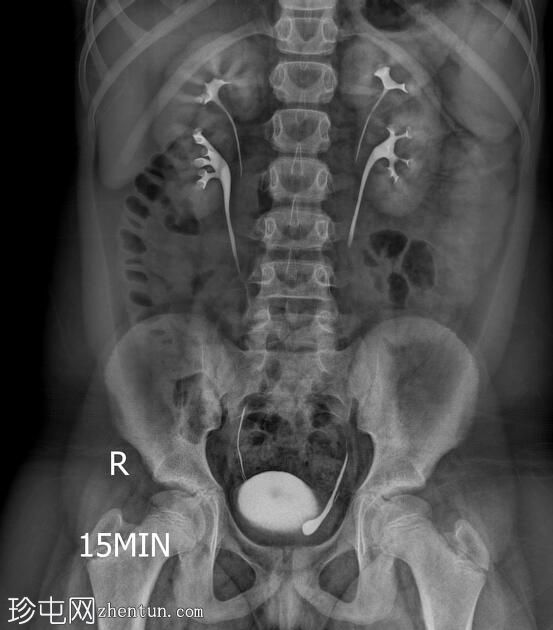

透视检查

正位

双侧肾盂肾盏系统及输尿管重复畸形。

左肾上极异位输尿管末端形成输尿管囊肿。

根据魏格特-迈耶定律,在完全性输尿管重复畸形的双肾病例中,上极和下极分别由独立的输尿管引流。上极输尿管通常存在异位开口,位于下极输尿管的内侧和下方,并常形成输尿管囊肿,正如本病例所示。